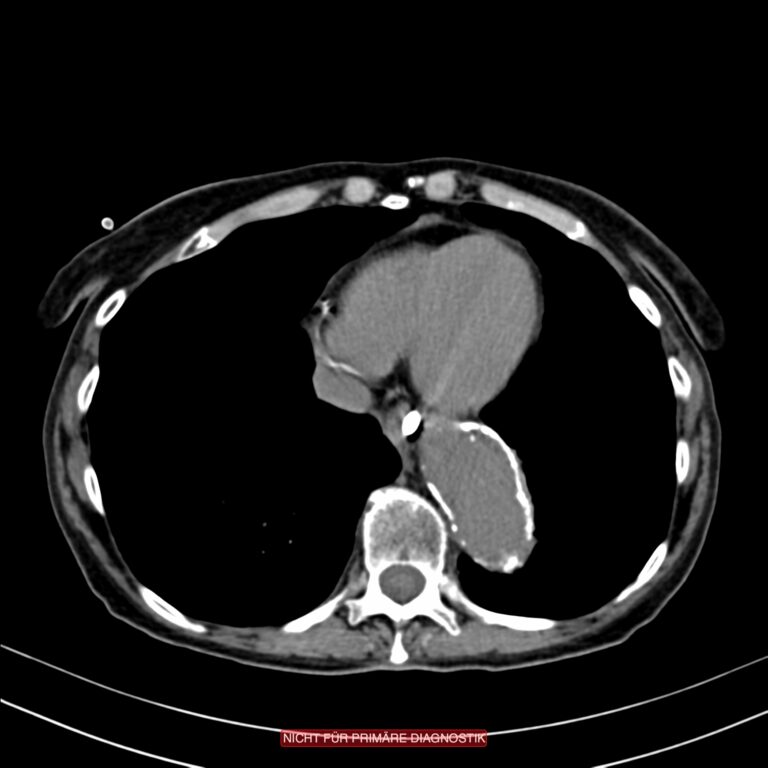

Sie sehen hier CT-Bilder einer mesenterialen Ischämie. Gut zu sehen sind zwei typische Zeichen der mesenterialen Ischämie.

Am Darm erkennt man eine sog. Pneumatosis intestinalis. Diese Lufteinschlüsse in der Darmwand sind Ausdruck der sich dort abspielenden Nekrose. Dabei bilden sich auf Grund von Fäulnissprozessen und durch den Zusammenbruch er Darmbarriere Gasbläschen, die im CT sichtbar werden.

Da der Darm über das portalvenöse Stromgebiet in die Leber drainiert wird, sammelt sich dort ebenfalls die Luft an. Diese Lufteinschlüssen in den Verzweigungen der Pfortader nennt man Pneumoportogramm.